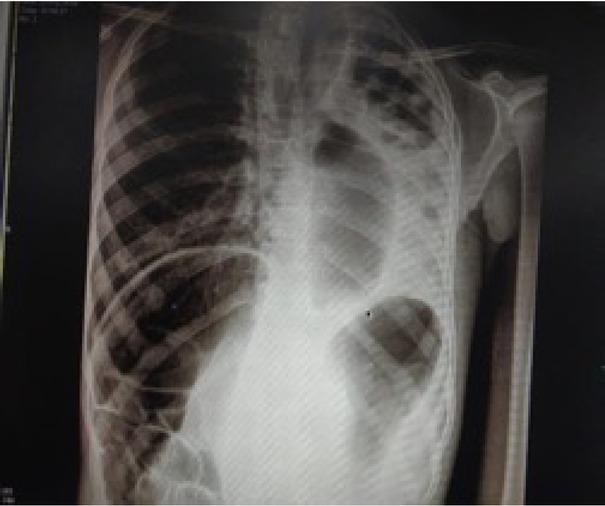

Figure 1